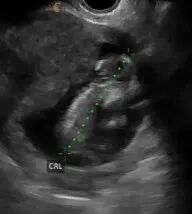

爱妈G一转眼宝宝已经6周了,虽然六周时的胎儿尚未有明显的人类特征,胎儿的体重通常还很轻微,难以具体测量。但它们正在迅速发展,并且这个阶段是整个孕期中发育最为迅猛的时期之一.在孕早期爱妈们都要经历一系列孕妈妈典型的症状,例如晨吐,疲劳,乳房胀痛等等,面对身体的各种变化和不适,希望可以给爱妈们更多的鼓励。期待准爸爸的二宝继续健康成长。

六周零三天的胎宝宝